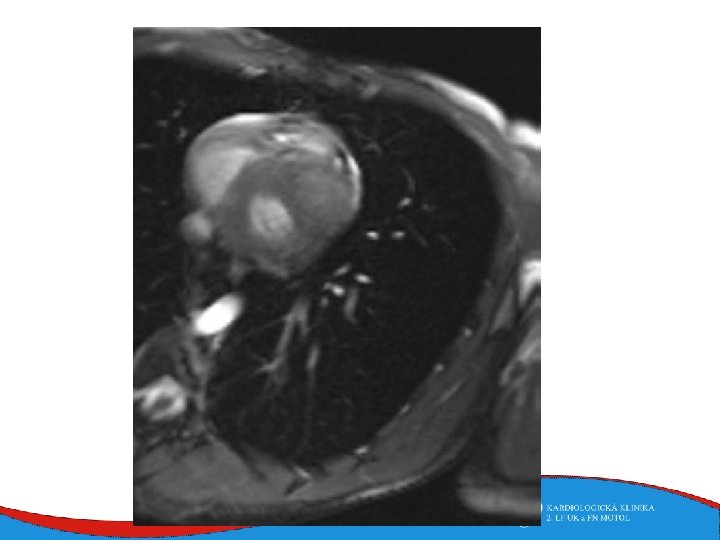

Diagnosis Family history Phisical examination ECG systolic murmur at the apex and lower left sternal border heterogenous LVH, patol. Q , QS, …. ECHO – golden standard MRI septal thickness more than 15 mm, papillary muscles hypertrophy, mitral anterior leaflet elongation, pressure gradient regions of myocarrdial fibrosis regions of late gadolinium enhancement (LGE) Stress test blood pressure responce ECG monitoring ventricular arrhythmia Selective coronarography

Left ventricular non-compaction Rare (cca 1: 7000) Primary genetic disease - Sarcomeric and mitochondrial genes ECHO Non-compacted myocardium especially in the apical part of the left ventricle

Left ventricular non-compaction • Signs and symptoms • Heart failure • Thromboembolic complications • LV trabecularization- predisposition • Anticoagulation therapy (systolic dysfunction) • DG – echo, MRI • Therapy – heart failure therapy, anticoagulation therapy

Tako-tsubo